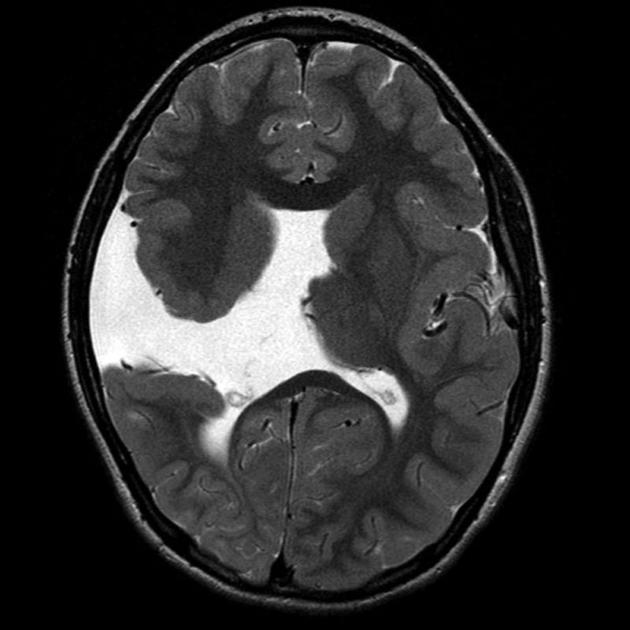

hot cross bun sign

hyperintensities of cerebellar peduncles